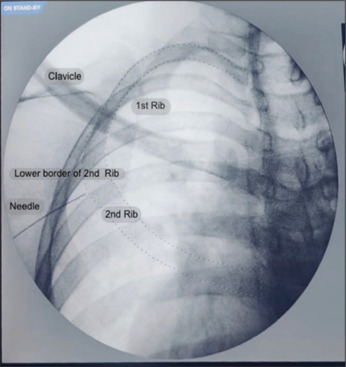

肋间臂神经阻滞-一个痛苦的谜题解码。

Intercostobrachial nerve block - A painful puzzle decoded.